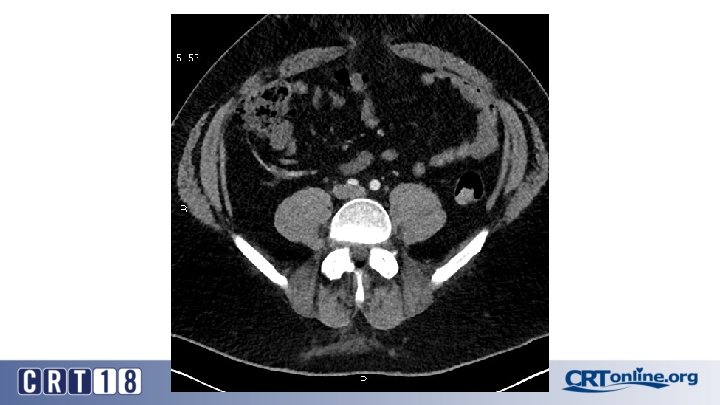

Blue Toe Syndrome

Returns Next day

Failed recanalization: BKA